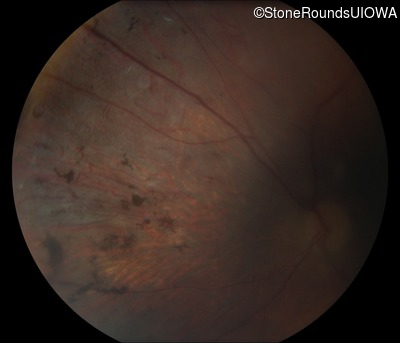

Fundus Photography - Right - 20/250

Exemplar